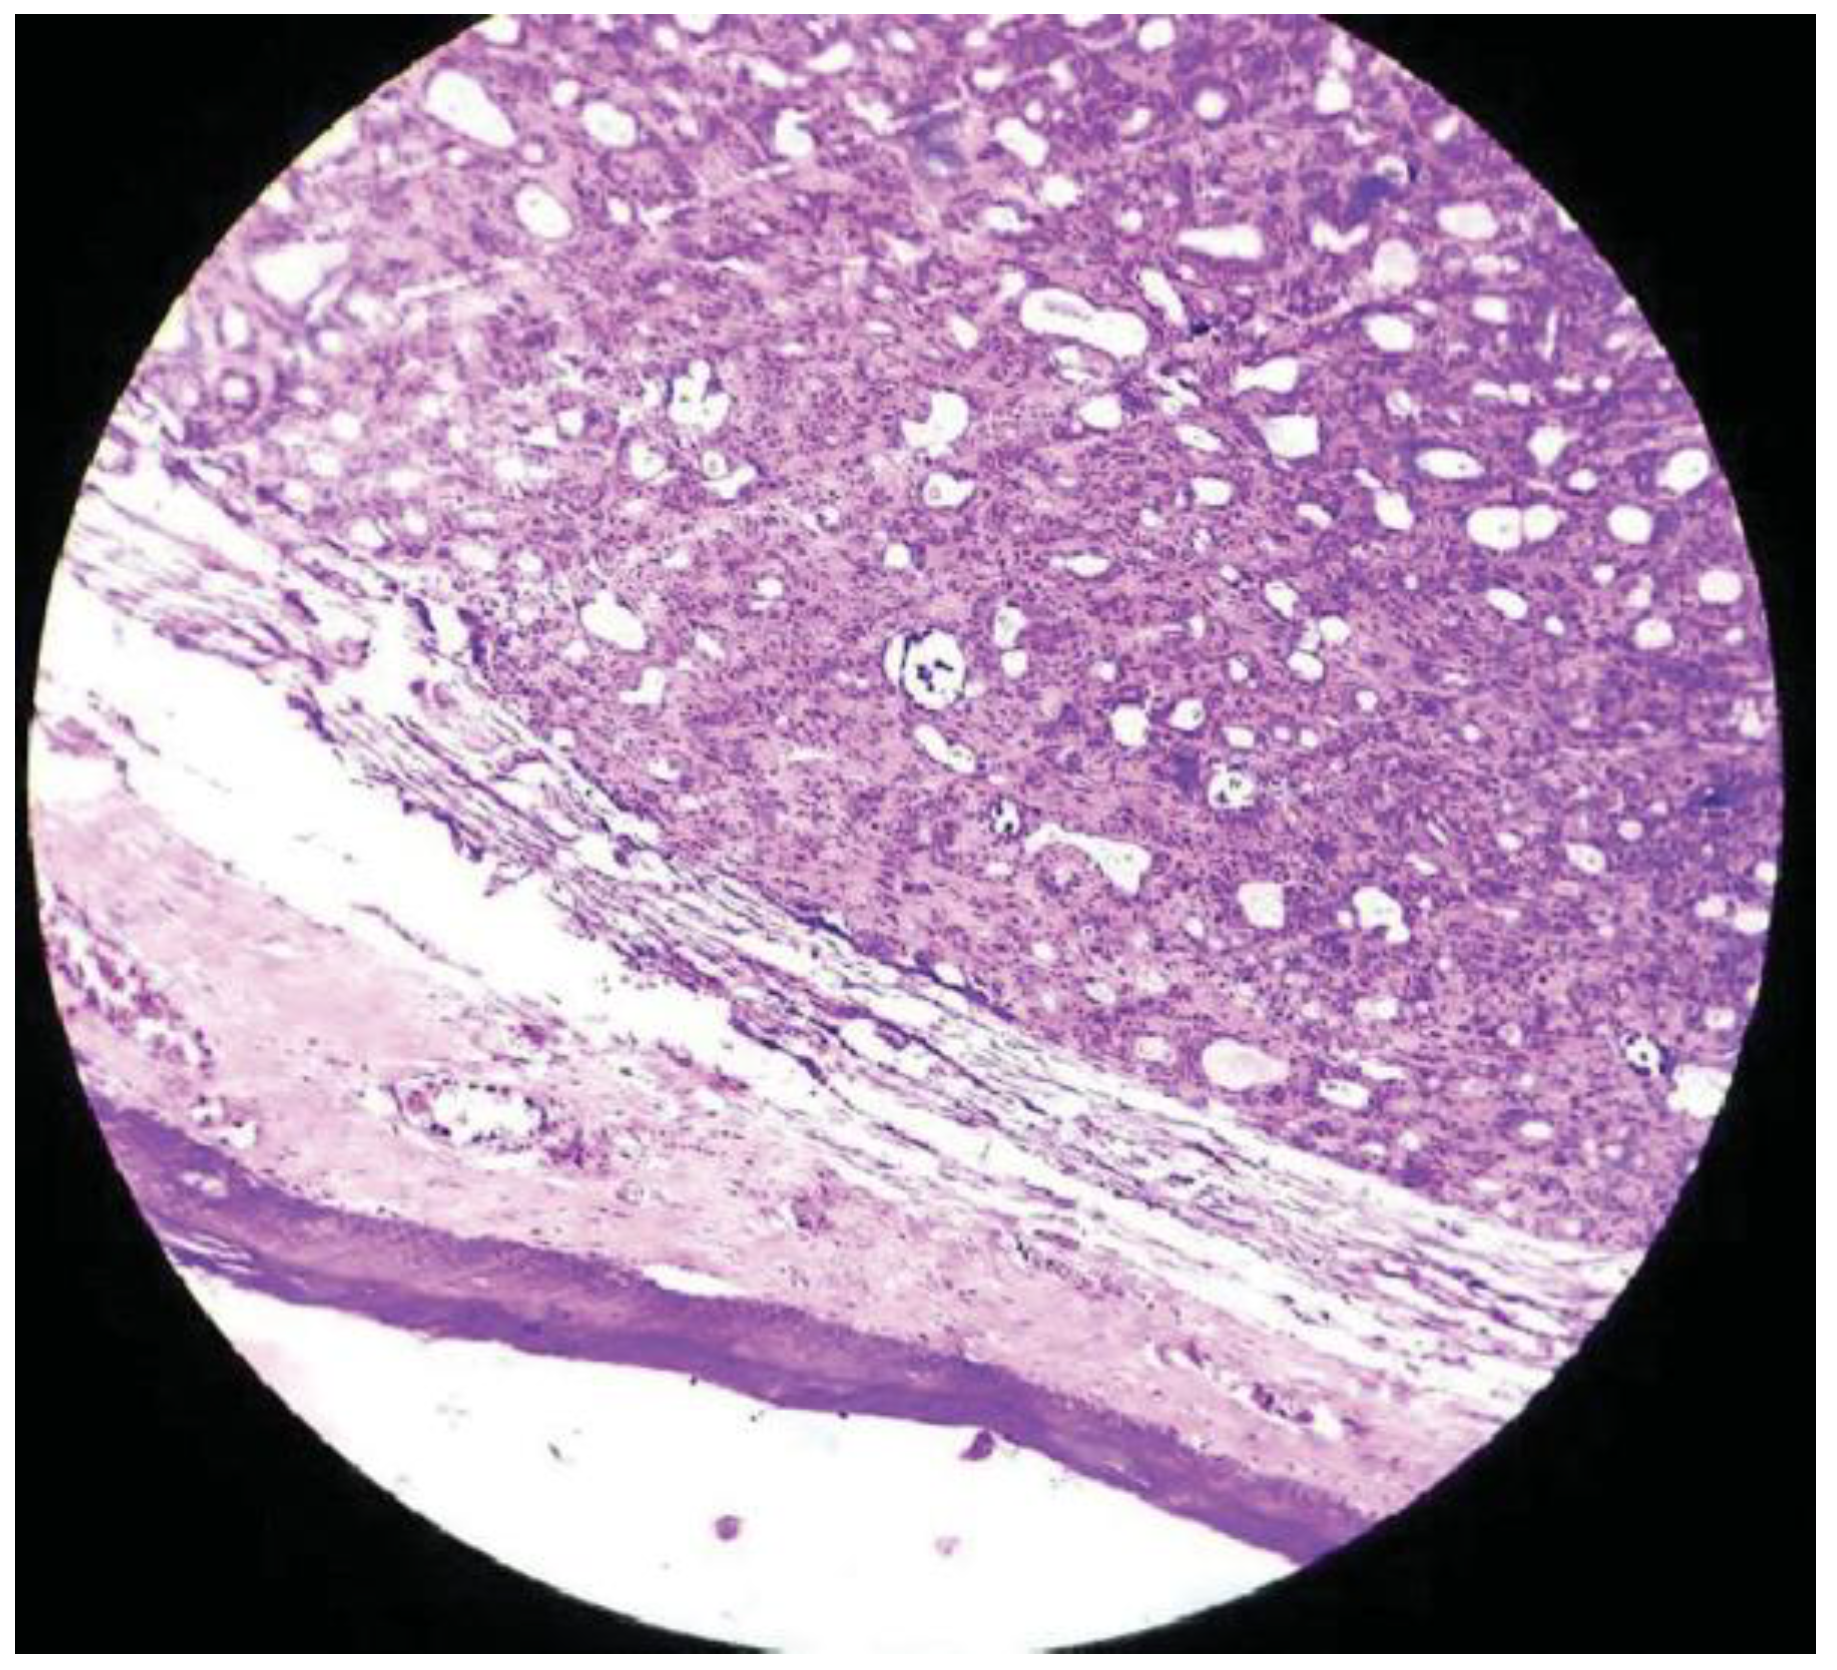

:Case Presentation

Discussion